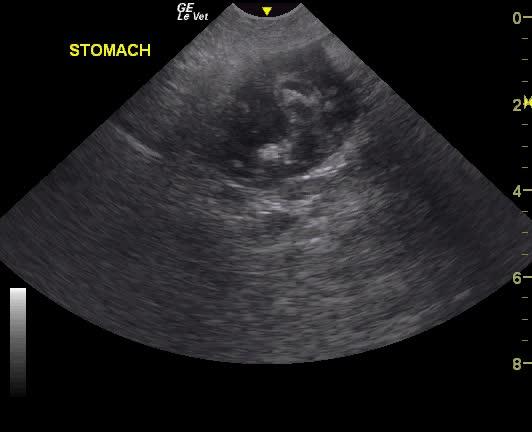

A NM Labrador with a history of foreign body ingestion was presented for intermittent diarrhea that had initially responded to bland diet, metronidazole and aminopentamide. More recently there had vomiting and he appeared uncomfortable. On physical examination, a palpable mass in the cranial abdomen was present. CBC was within normal limits and serum biochemistry showed elevated phosphate low BUN.